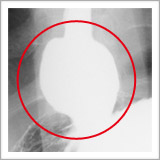

検査をすると、胃と食道の境目がゆるくて胃の一部が食道側に飛び出し(図1、図2)、一度胃に入ったバリウムが食道に戻ってきます(図3)

図2 |

| 胃の中から、胃の入り口を見上げた写真です。本当は締まってなくてはいけない胸とお腹の境い目が大きく開いています。 |